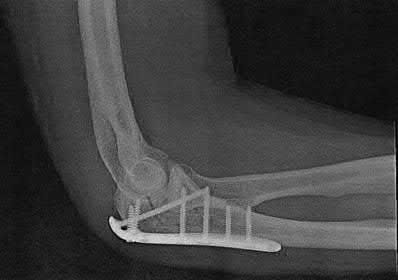

Figures A-C are the radiographs of a 26-year-old male who presents to the emergency department following a motocross accident. Two attempts at a closed reduction by the on-call orthopedic resident were unsuccessful. Figures D and E are the pre-operative axial CT-images that were obtained. The patient undergoes surgical fixation seen in Figure F. Limitations in post-operative dorsiflexion is likely influenced by which of the following?

The rare Bosworth fracture-dislocation is a posterior dislocation of the fibula which becomes entrapped behind the tibia. As demonstrated in this vignette, these injuries are extremely difficult to close reduce secondary to the ridge of the posterolateral distal tibia. The irreducible nature of this injury is a known risk factor for the development of compartment syndrome. The CT images further demonstrate fracture extension to the posteromedial rim (“posterior pilon variant”). In this situation, the only effective method to reduce the fracture is through an open posterolateral approach with the interval between the flexor hallucis longus and the peroneal tendons. This is the same approach that is utilized for fixation of the posterolateral fragment and fibula. Loss of dorsiflexion has been demonstrated following this fracture pattern with posterior fixation. The positioning of the plates in Figure F suggests the

utilization of a posterolateral approach.

Figures A-C: The initial radiographs reveal the posterior subluxation of the talus with associated posterior subluxation of the fibula without significant coronal plane deformity. This deformity should raise the suspicion of a Bosworth fracture-dislocation, especially if closed reduction is not successful. Figures D and E: Axial CT images demonstrating Bosworth fracture-dislocation of the fibula entrapped behind the tibia. Also, note the fracture extension to the posteromedial rim in this posterior pilon variant.

Figure F: Positioning of the plate suggests a posterolateral approach to address both the fibula and posterior malleolus fractures.